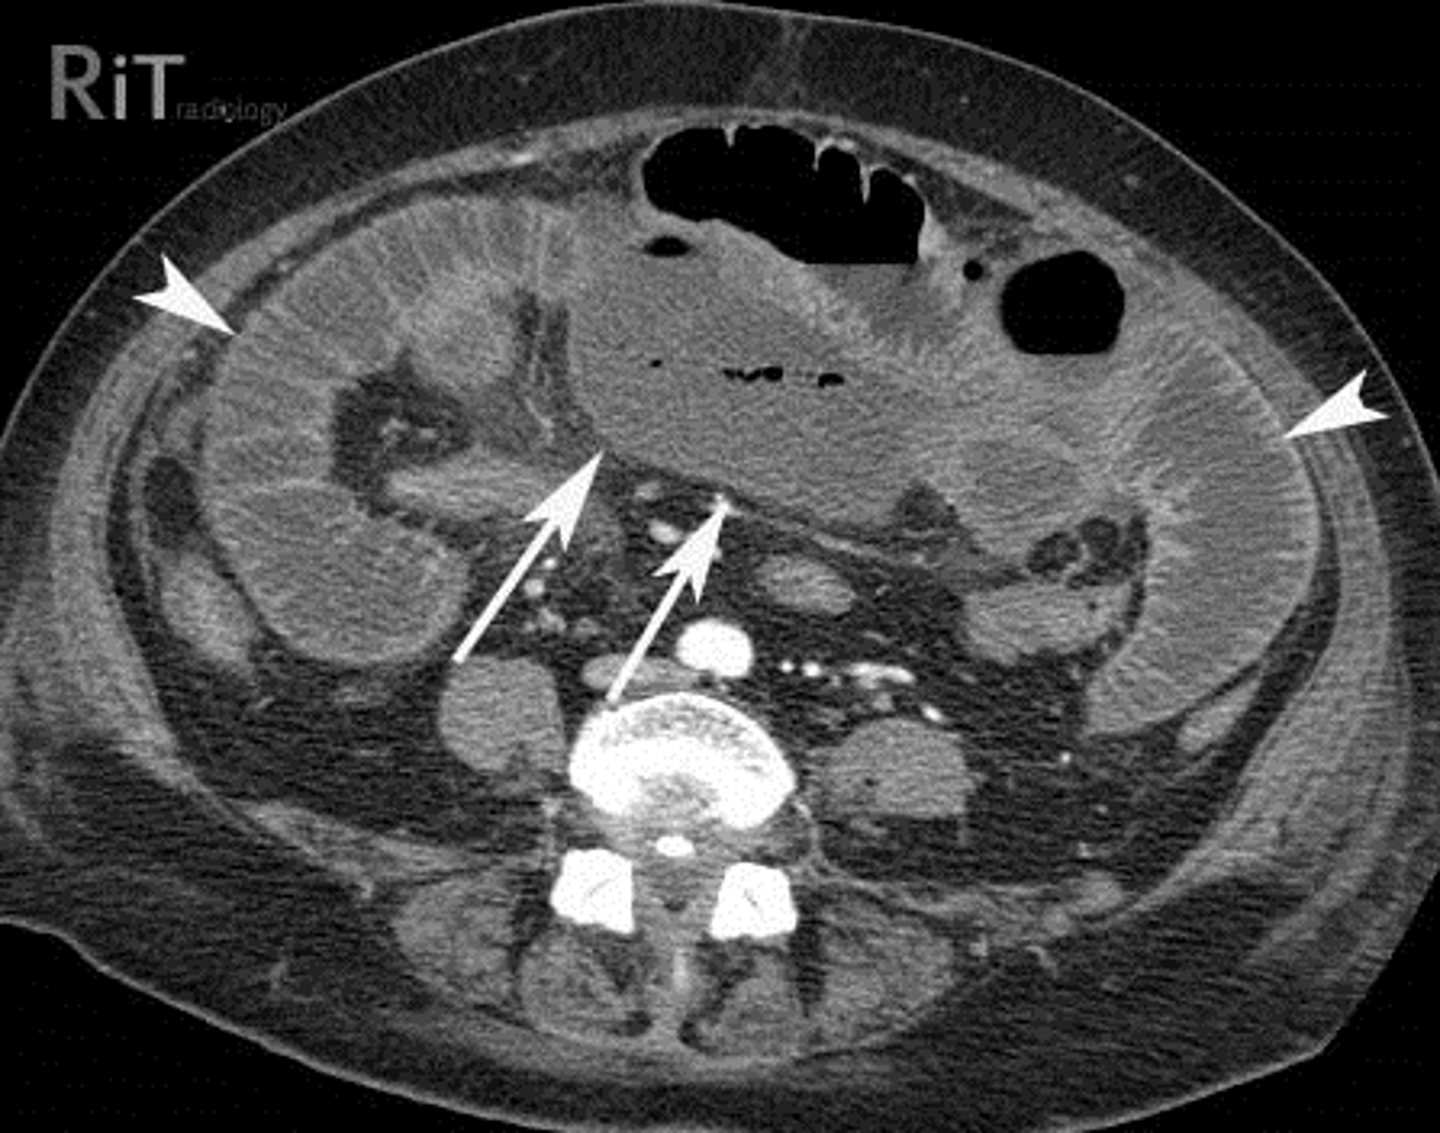

CT with IV contrast of SBO.

SOLID BLACK ARROWS: multiple fluid- and contrast filled dilated loops of small bowels.

WHITE ARROWS: Collapsed colon

DOTTED BLACK ARROW: Right renal cyst

Partial SBO

SOLID BLACK ARROW (gas passing into colon)

DOTTED WHITE ARROW: small bowel is disproportionately dilated

SOLID WHITE ARROWS: Clips from prior surgery

A partial or incomplete mechanical SBO - allows some gas to pass the point of obstruction. Can be confusing as gas may pass into the colon and be visible long after the large bowel would be expected to be devoid of gas.

The important observation is that the small bowel is DISPROPORTIONATELY DILATED compared with the large bowel, a finding suggestive of SBO.

Partial or incomplete small bowel obstructions occur more often in patients in whom adhesions are the etiologic factors. Notice the clips (solid white arrows) attesting to prior surgery.